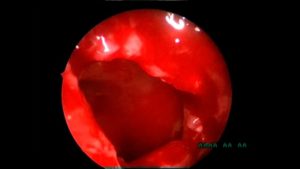

эндоскопическая гайморотомия

Эндоскопический доступ – это доступ без разрезов из полости носа или (реже) из полости рта. В стенке гайморовой пазухи делается прокол, через который в нее вставляется эндоскоп.

Прокол в диаметре составляет не более 5 мм. Изображение с микроэндоскопа передается на монитор и хирург имеет возможность видеть внутреннее строение пазухи в многократном увеличении.

С помощью специальных эндоскопических инструментов в пазухе проводятся все необходимые манипуляции (вычищение, удаление патологического содержимого, удаление полипов, кист, инородных тел, взятие материала на гистологическое исследование).